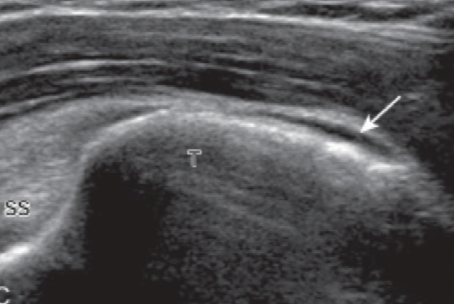

자세 3. 봉우리빗장관절 및 봉우리밑-세 모근밑 윤활주머니

봉우리빗장관절(acromioclavicular joint)은 탐촉자를 빗장뼈(clavicle) 먼쪽(distal)에 빗관상면(coronal-oblique plane)으로 놓고 손으로 만지면서 그 위치를 찾거나, '자세 1' 에서처럼 가로축 방향으로 놓은 탐촉자를 그대로 어깨 위로 옮기면서 찾아간다. 관절을 이루는 두 뼈는 높은 에코로 보이고, 관절강(joint cavity)은 낮은 에코로 나타난다. 탐촉자를 관절 위에 놓은 상태에서, 탐촉자를 잡지 않은 검사자의 반대 손(free hand)으로 환자의 팔(검사받는 쪽)을 잡고 당기면서 검사하면, 관절의 이완(laxity)을 알 수 있다.

다른 방법은 환자의 손(검사받는 쪽)을 반대편 어깨 위로 올려서 앞뒤로 움직여보면 관절강이 넓어지는 것을 알 수 있다. 탐촉자를 바깥쪽으로 좀 더 옮기면 깊은 부위에 위팔뼈(humerus)의 큰 거 친면이 보이는데, 이때 봉우리밑 -세 모근밑 윤활주머니(subacromial -subdeltoid bursa)의 아래쪽(dependent portion)에 고인 액체를 관찰할 수 있다.